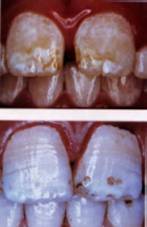

But less about other dangers, for the moment. We want to bring you images of dental fluorosis. They will act as a rough guide to the severity of your condition.

Six types of fluorosis (Source: Fluoride Free, Ireland):

Four pictures of fluorosis (Source: Fluoride: Protected Pollutant or Panacea? Canada):

Five pictures of fluorosis (source: Fluoride Action Network, USA):

Six pictures of fluorosis (source: Provided by Dr Susheela, India):